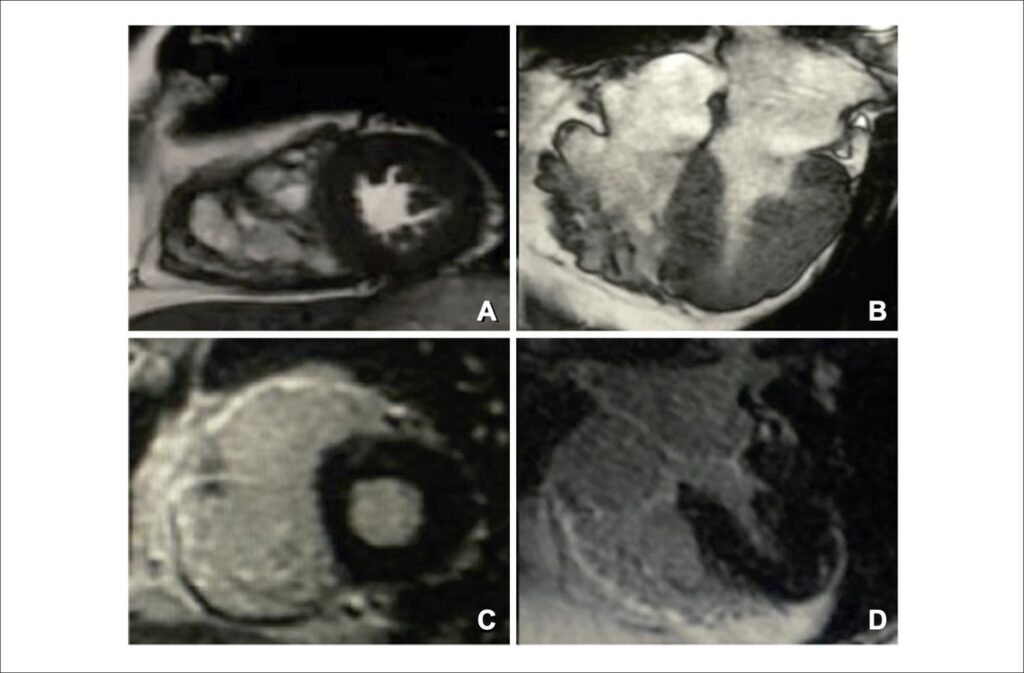

Achado Incidental de Cardiomiopatia Arritmogênica do Ventrículo Direito em Homem de 72 Anos Admitido com Síndrome Coronariana Aguda

A cardiomiopatia arritmogênica do ventrículo direito (CAVD) – também conhecida como displasia arritmogênica do ventrículo direito (VD) – é uma doença hereditária caracterizada pela perda progressiva de cardiomiócitos do VD e substituição por tecido fibrogorduroso. Essa substituição pode retardar a condução intraventricular e contribuir para arritmias ventriculares por meio de um mecanismo de macrorreentrada relacionado à fibrose. Assim, a CAVD é uma das principais causas de parada cardíaca arrítmica em jovens e atletas.